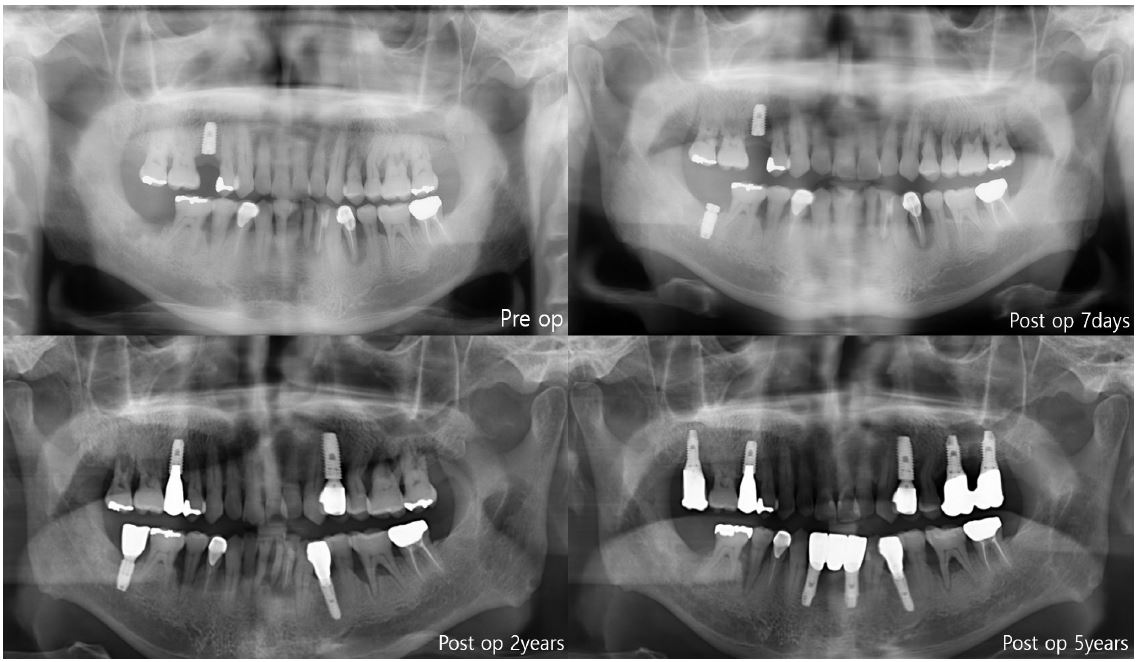

In the first case of failure, the patient had no specific medical history. The implant was removed at 6 years and 11 months (Fig. 3). In the second case, the patient had diabetes mellitus, and a smoking history. Also, GBR was performed with Xenograft and Bio-Oss. The implant was removed at 8 years and 3 months (Fig. 4). In the third case, the patient had radiotherapy history for tonsil cancer. The implant was removed at 4 years and 10 months (Fig. 5). In the fourth case, the patient had diabetes mellitus. The implant was removed, and another implant was immediately placed at four months (Fig. 6).

The first three cases of failure were classified as late failures. In one out of four cases, implant was removed at four months after implantation, and this was classified as an early failure (Fig. 6).